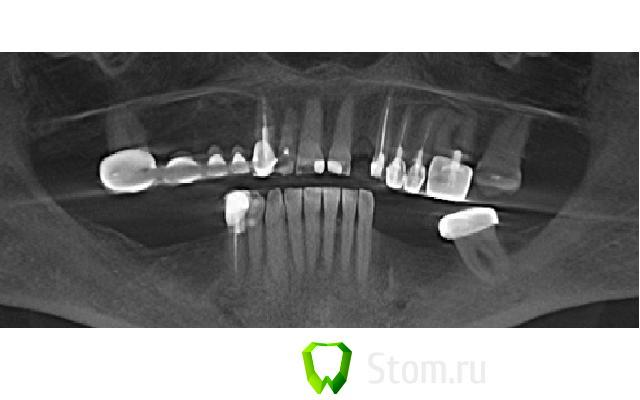

alexandr_spb Опубликовано 6 февраля, 2012 Поделиться Опубликовано 6 февраля, 2012 Добрый день коллеги! составляю план . поправте если что не правильно говорю и делаю.22 зуб - планируется имплантация 3.0 биогоризонт с предварительной аугментацией альвеолярного отростка по методике split control+биоосс+своя костная стружка+мембрана. кт прилагаю. Пациент гарантийный по этой причине костные блоки пока не рассаматриваются. Ссылка на комментарий

GIC77 Опубликовано 11 февраля, 2012 Поделиться Опубликовано 11 февраля, 2012 Добрый день коллеги! составляю план . поправте если что не правильно говорю и делаю.22 зуб - планируется имплантация 3.0 биогоризонт с предварительной аугментацией альвеолярного отростка по методике split control+биоосс+своя костная стружка+мембрана. кт прилагаю. Пациент гарантийный по этой причине костные блоки пока не рассаматриваются.В вашем случае, вполне достаточно места для расщепления гребня Ссылка на комментарий